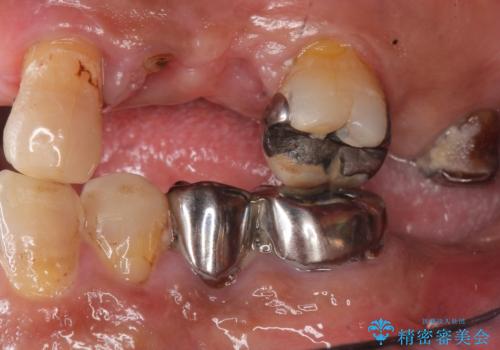

- 交通事故により前歯が折れたことを主訴に来院された患者様です。

精査したところ、前歯以外にも歯が折れており、上の歯の多くが保存不可能な状態でした。

保存可能な2本の歯を用いて、マグネットデンチャー(磁性アタッチメントを用いた入れ歯)による治療を行いました。

下顎の治療に関しては、ご予算によりご希望されませんでした。